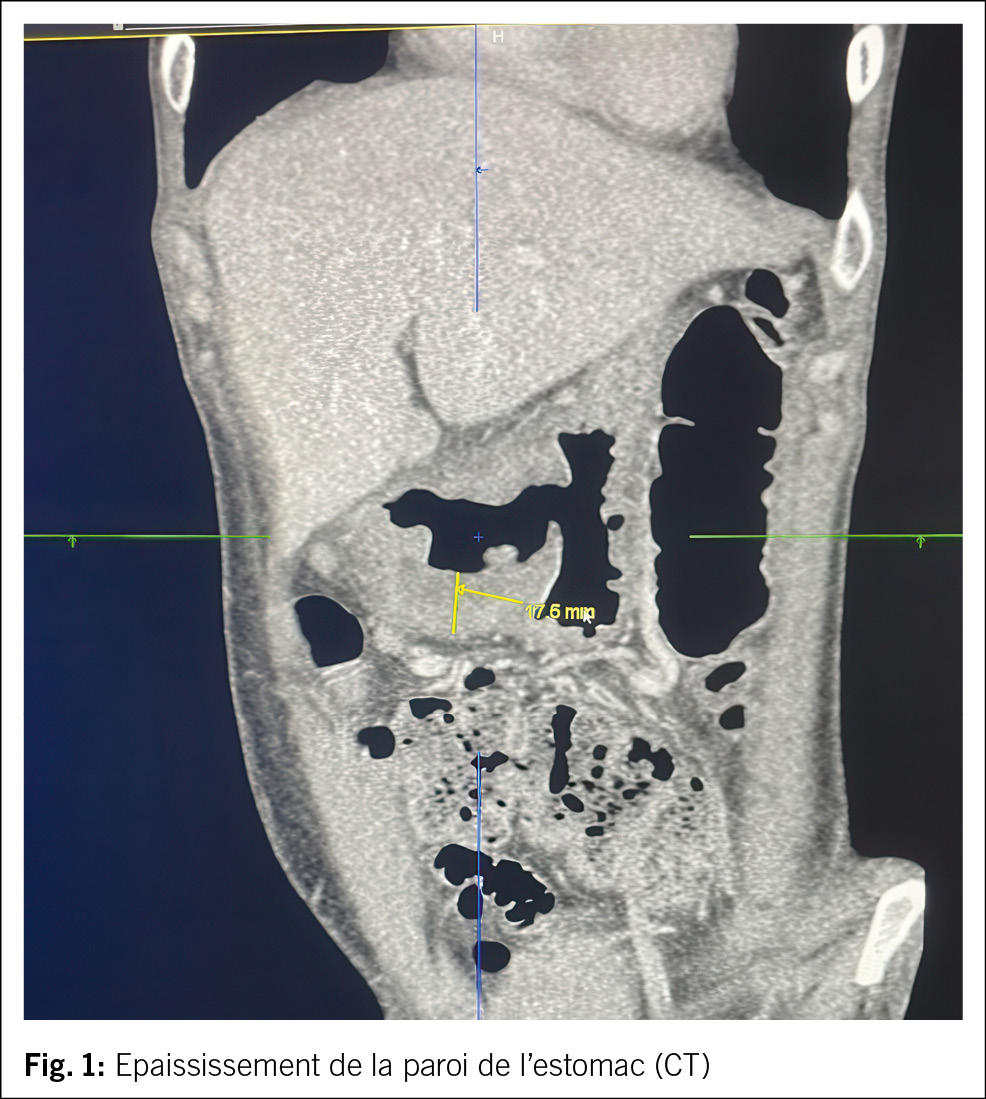

À la dernière hospitalisation, 4 mois après la 2ième OGD, elle ne pesait qu’encore 41 kg, mais cette fois aussi son Hb est à la baisse avec une valeur initiale de 108 g/l, le lendemain même à 96 g/l. De plus, nous trouvons un syndrome inflammatoire avec une leucocytose à 27.7 g/l et une CRP à 59 mg/l. En plus des épigastralgies, nous constatons aussi des ganglions axillaires et inguinaux, indolores. Un 2ème scanner abdominal montre toujours un épaississement pariétal de la partie basse de l’estomac et de la région du pylore (Fig. 1). Une sérologie virale et un test quantiferon reviennent négatifs. Une 3ième gastroscopie sous intubation protective (risque de broncho-aspiration) montre une grande ulcération antrale et intra-pylorique (Fig. 2), sténosante, très suspecte d’une néoplasie, ainsi que des signes d’une hémorragie digestive haute avec 350 ml d’hématine dans l’estomac. Des biopsies sont prélevées.